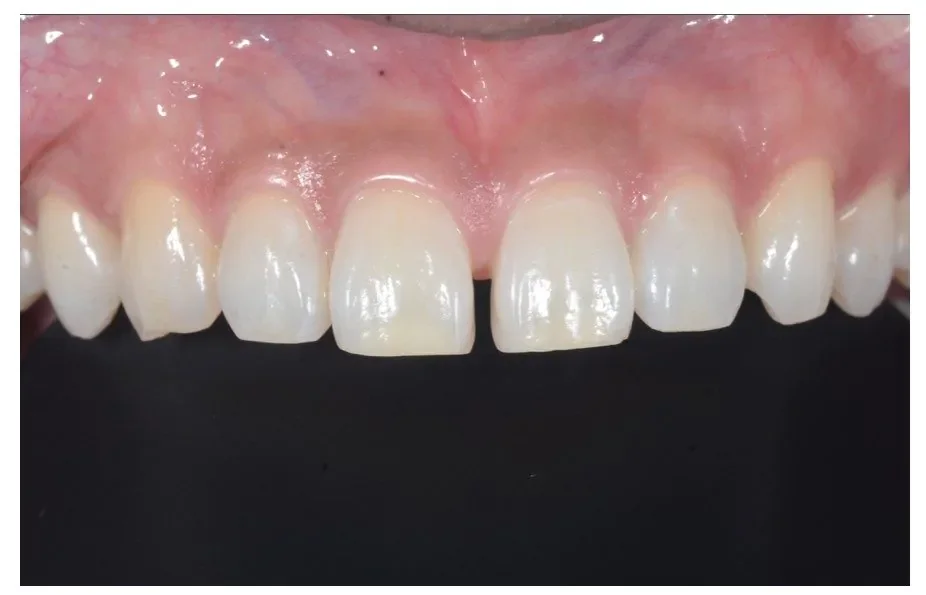

Before

After

ダイレクトボンディングの症例2

2週間、3回 / 88,000円リスク・副作用:経年的に歯間が開いてくる可能性及び接着低下によりレジン脱離、レジン周囲変色